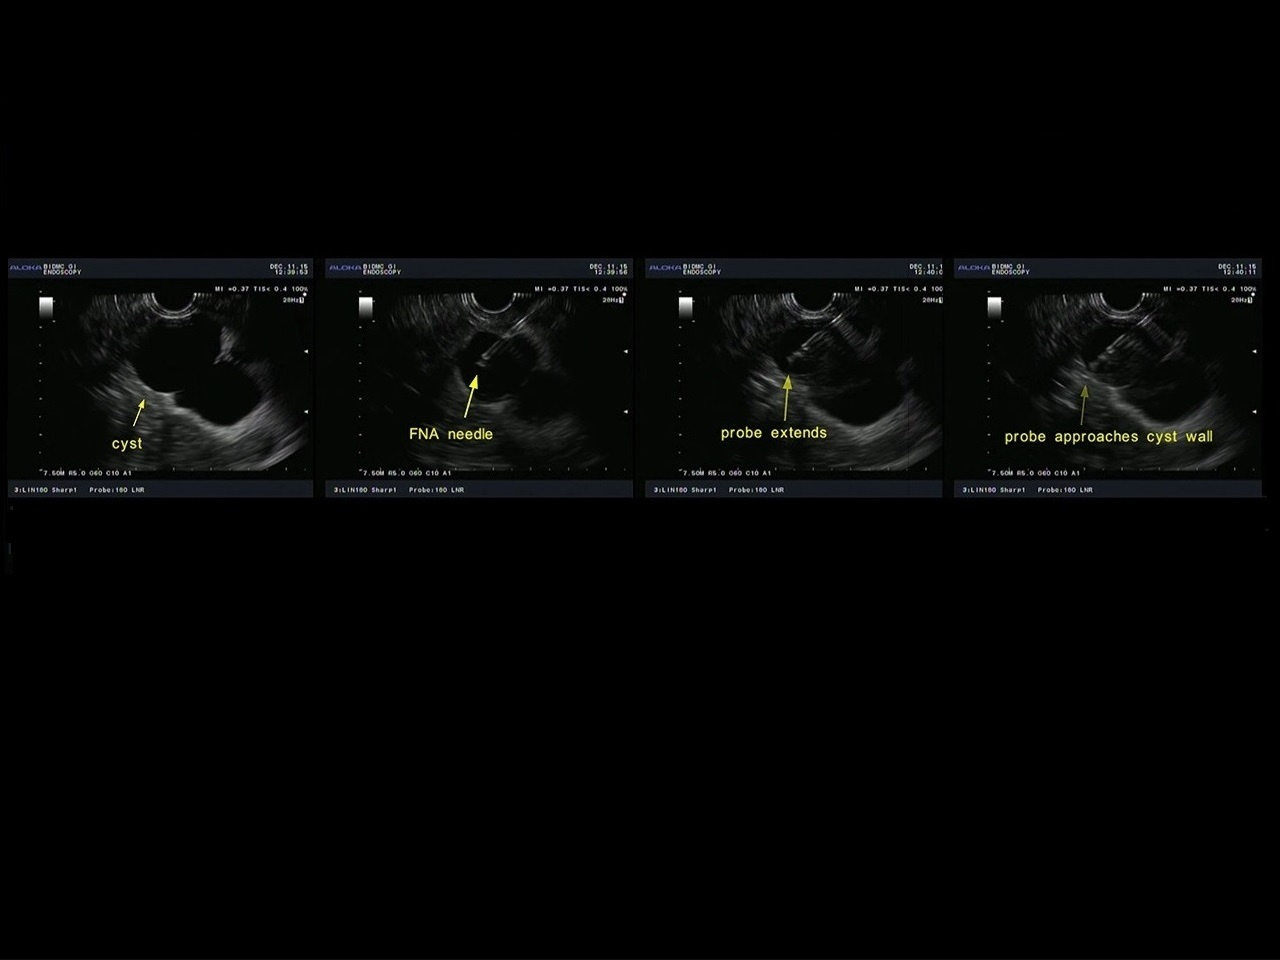

Figure 2. EUS images showing data collection from one of multiple spatial locations in a pancreatic cyst.

Encouraged by our quite successful application of light scattering spectroscopy in the esophagus, we decided to try it for diagnosing malignancy in pancreatic cysts. The most challenging part was to develop a tiny fiber optic probe, compatible with the miniature, half millimeter in diameter, EUS-FNA needle, capable of enhancing the contribution of the light scattering signal coming from the epithelial cells. Our interdisciplinary team solved this problem by constructing a spatial gating light scattering spectroscopy (LSS) probe, which uses the fact that the backscatter signal coming from epithelial cells decreases with the distance between the source and detector fibers significantly faster than the multiple scattering signal (Fig. 1). With this probe our new LSS fine needle aspiration compatible instrument provides highly accurate in vivo identification of the malignant potential of pancreatic cysts during endoscopy (Fig 2. and Fig. 3).

Figure 3. Collecting data with the new in vivo LSS clinical system for detection of early cancer in pancreatic cystic lesions during a routine endoscopic ultrasound-guided fine needle aspiration (EUS-FNA) procedure. Douglas K. Pleskow, MD (center) is controlling the position of the LSS fiber optic probe inside the pancreatic cyst using EUS guidance and Le Qiu, PhD (front right) is collecting the LSS cyst data.